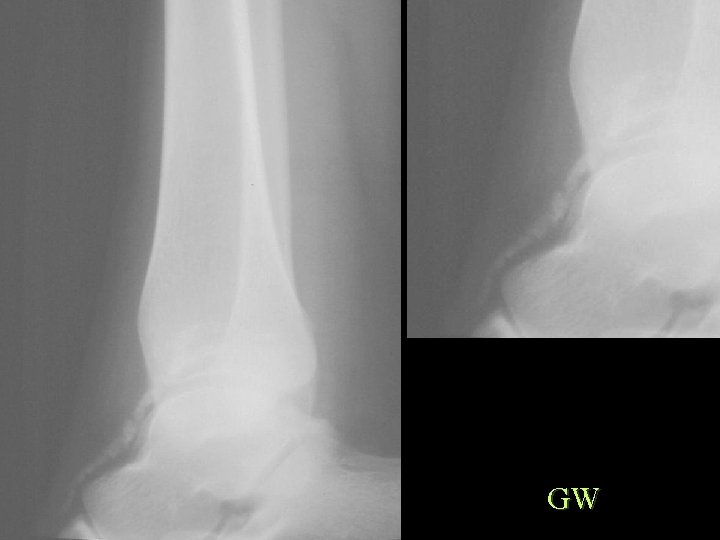

Calcification By Shape Linear and Curvilinear • Arterial – Atheroma, Aneurysm, Diabetes, HPT, Progeria, Werner’s • Nerve – Leprosy, Neurofibromatosis • Tendon and Ligament – Tendinitis, AS, Ochronosis, Fluorosis, Diabetes • Injection – Bismuth, Arsenic, Quinidine • Parasite – Cysticercosis, Guinea worm, Loa, Armillifer armillatus

GW